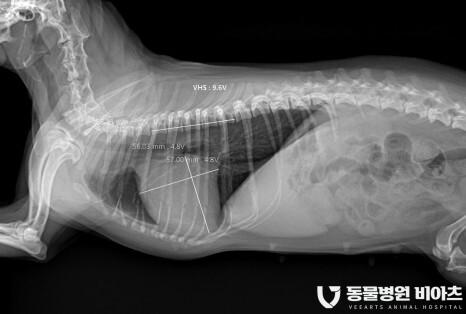

4. 엑스레이/초음파

엑스레이 (VHS, VLAS)

방사선 촬영

방사선 촬영에서는

심장의 비대 정도

VHS(Vertebral heart size) 와

VL(Vertebral left atrial size)

를 측정합니다.